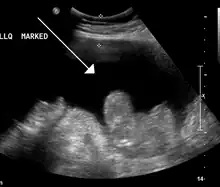

- Échographie abdominale : très sensible pour détecter les épanchements liquidiens, elle permet d'observer une lame d'ascite, notamment au niveau des flancs, de l'espace interhépatorénal (de Morison) et du cul-de-sac de Douglas